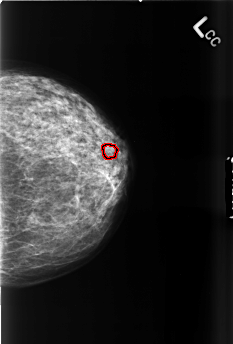

B_3460_1.LEFT_CC

FILE: B_3460_1.LEFT_CC.OVERLAY

TOTAL_ABNORMALITIES 1

ABNORMALITY 1

LESION_TYPE CALCIFICATION TYPE PUNCTATE-PLEOMORPHIC DISTRIBUTION CLUSTERED

ASSESSMENT 4

SUBTLETY 3

PATHOLOGY BENIGN